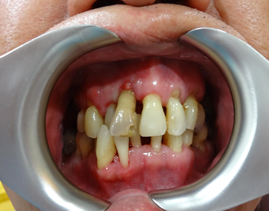

This is how his dentition and gum condition when he first saw me. Scaling was done prior to photo taking. His oral hygiene was compromised, and one of the upper front incisor is wobbly, with gum boil. Thorough examination for his teeth and gum was done. He wanted gum therapy and hope to save his other teeth, if possible. He also understood that gum therapy is a tedious procedure and needs his co-operation in term of good ora hygiene home care routine.